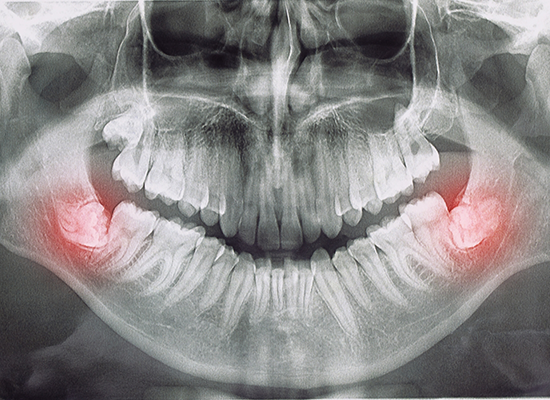

The wisdom teeth, sometimes called the third molars, are found at the very back of the mouth – and in all honesty, they’re often more trouble than they’re worth since they can cause various dental issues. Wisdom tooth extraction is a common procedure used to prevent pain, crowding, or other potential complications that are caused by impacted or misaligned wisdom teeth. To learn more about the wisdom tooth extraction process, or to schedule a consultation to see if it’s time for your wisdom teeth to come out, don’t hesitate to contact our office in Colorado Springs.

Right before the wisdom tooth extraction procedure, we’ll numb your mouth to ensure that you’re comfortable. The process by which the teeth are extracted depends on whether they’re impacted or not. If the teeth are impacted, a small incision may be made to remove them in smaller sections. In other cases when they’re erupted as anticipated, they can be removed using forceps.